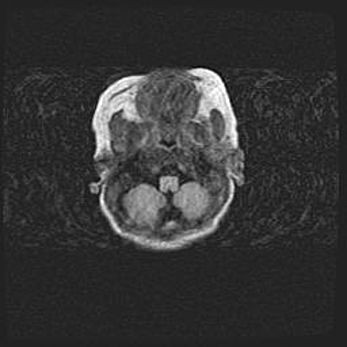

Мальформация Денди-Уокера. Киста задней черепной ямки.

Агенезия мозолистого тела.

Возраст: 2,5 месяца

Вес: 2420 г

Пол: женский

Окружность головы: 37 см

Срок гестации: 32 недели

Мальформация Денди—Уокера — редкий вид патологии ЦНС, представляющий собой врожденный порок развития каудального отдела ствола и червя мозжечка, ведущий к неполному раскрытию срединной (Мажанди) и латеральных (Лушка) апертур IV желудочка мозга. Для этогно синдрома характерна триада симптомов: гипотрофия червя мозжечка и/или полушарий мозжечка, кисты задней черепной ямки, гидроцефалия различной степени. В 70% случаев порок сочетается и с другими аномалиями головного мозга, в частности с агенезией мозолистого тела.